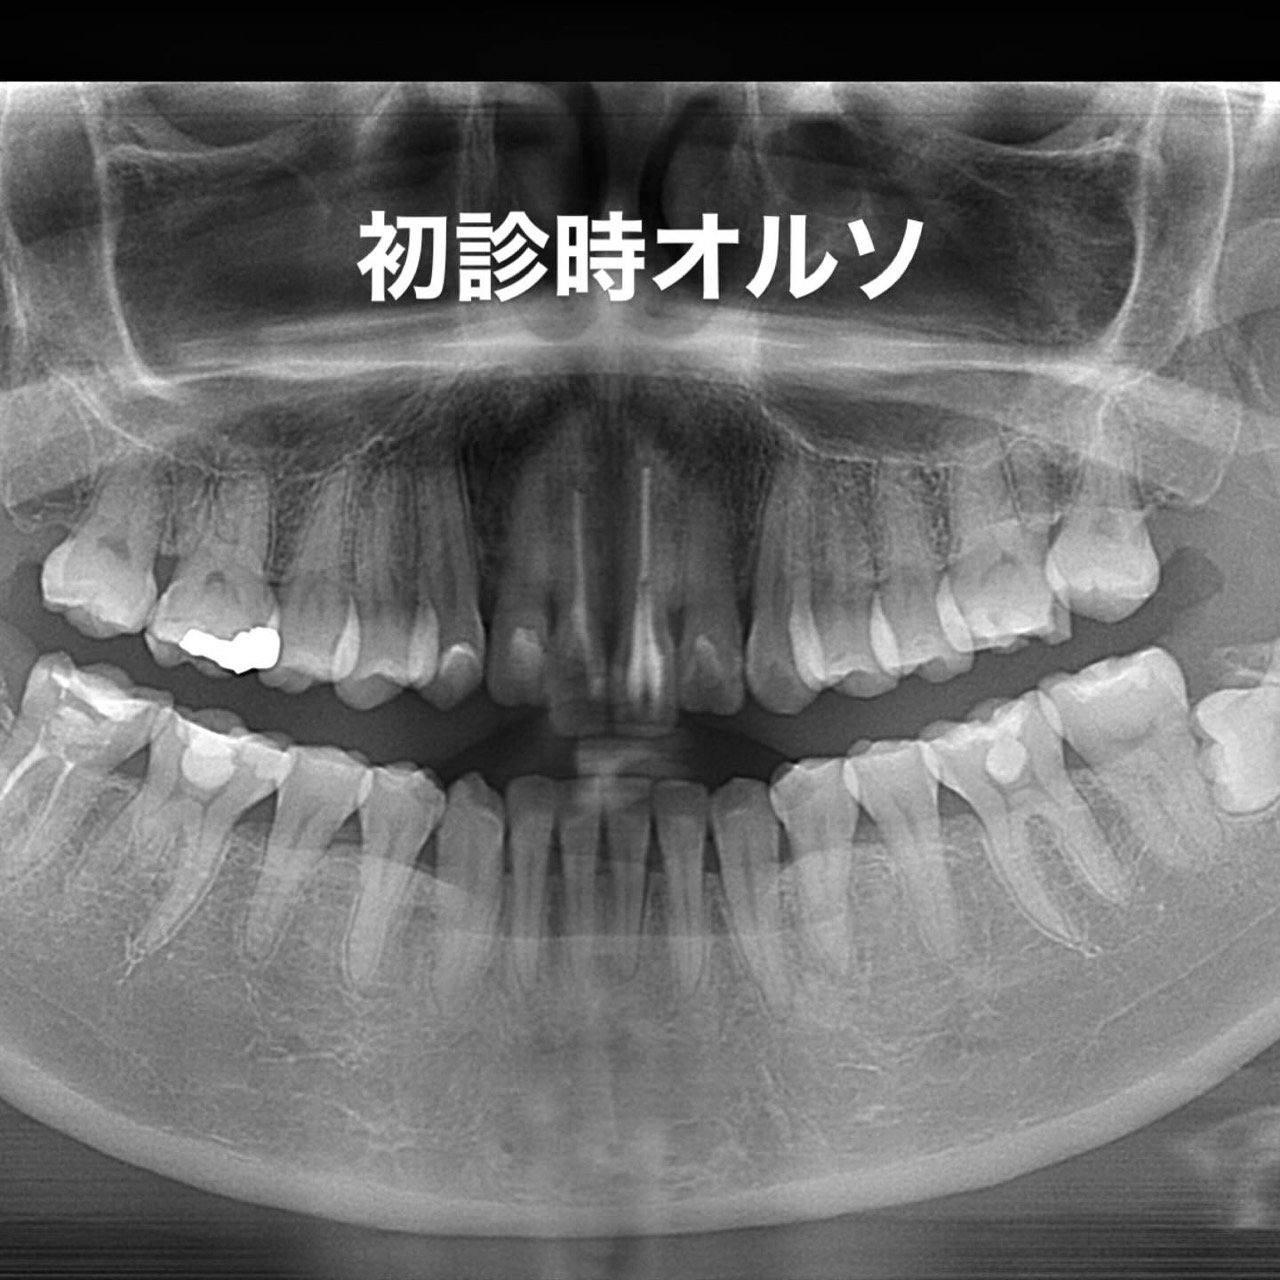

Case031

前歯が虫歯なのと、保険のプラスチックで大きく治療されていて色が悪いこと、歯並びが出っ歯気味であることを気にしてセラミックにしたいという主訴で来院された患者様です。

虫歯が大きかったところは神経治療をきちんと行い、

初診時を含めてトータル4回のご来院で完了です。

今回は前歯を下げる、歯列を整える、白すぎず自然に綺麗に見える色というご希望に沿って治療しました。